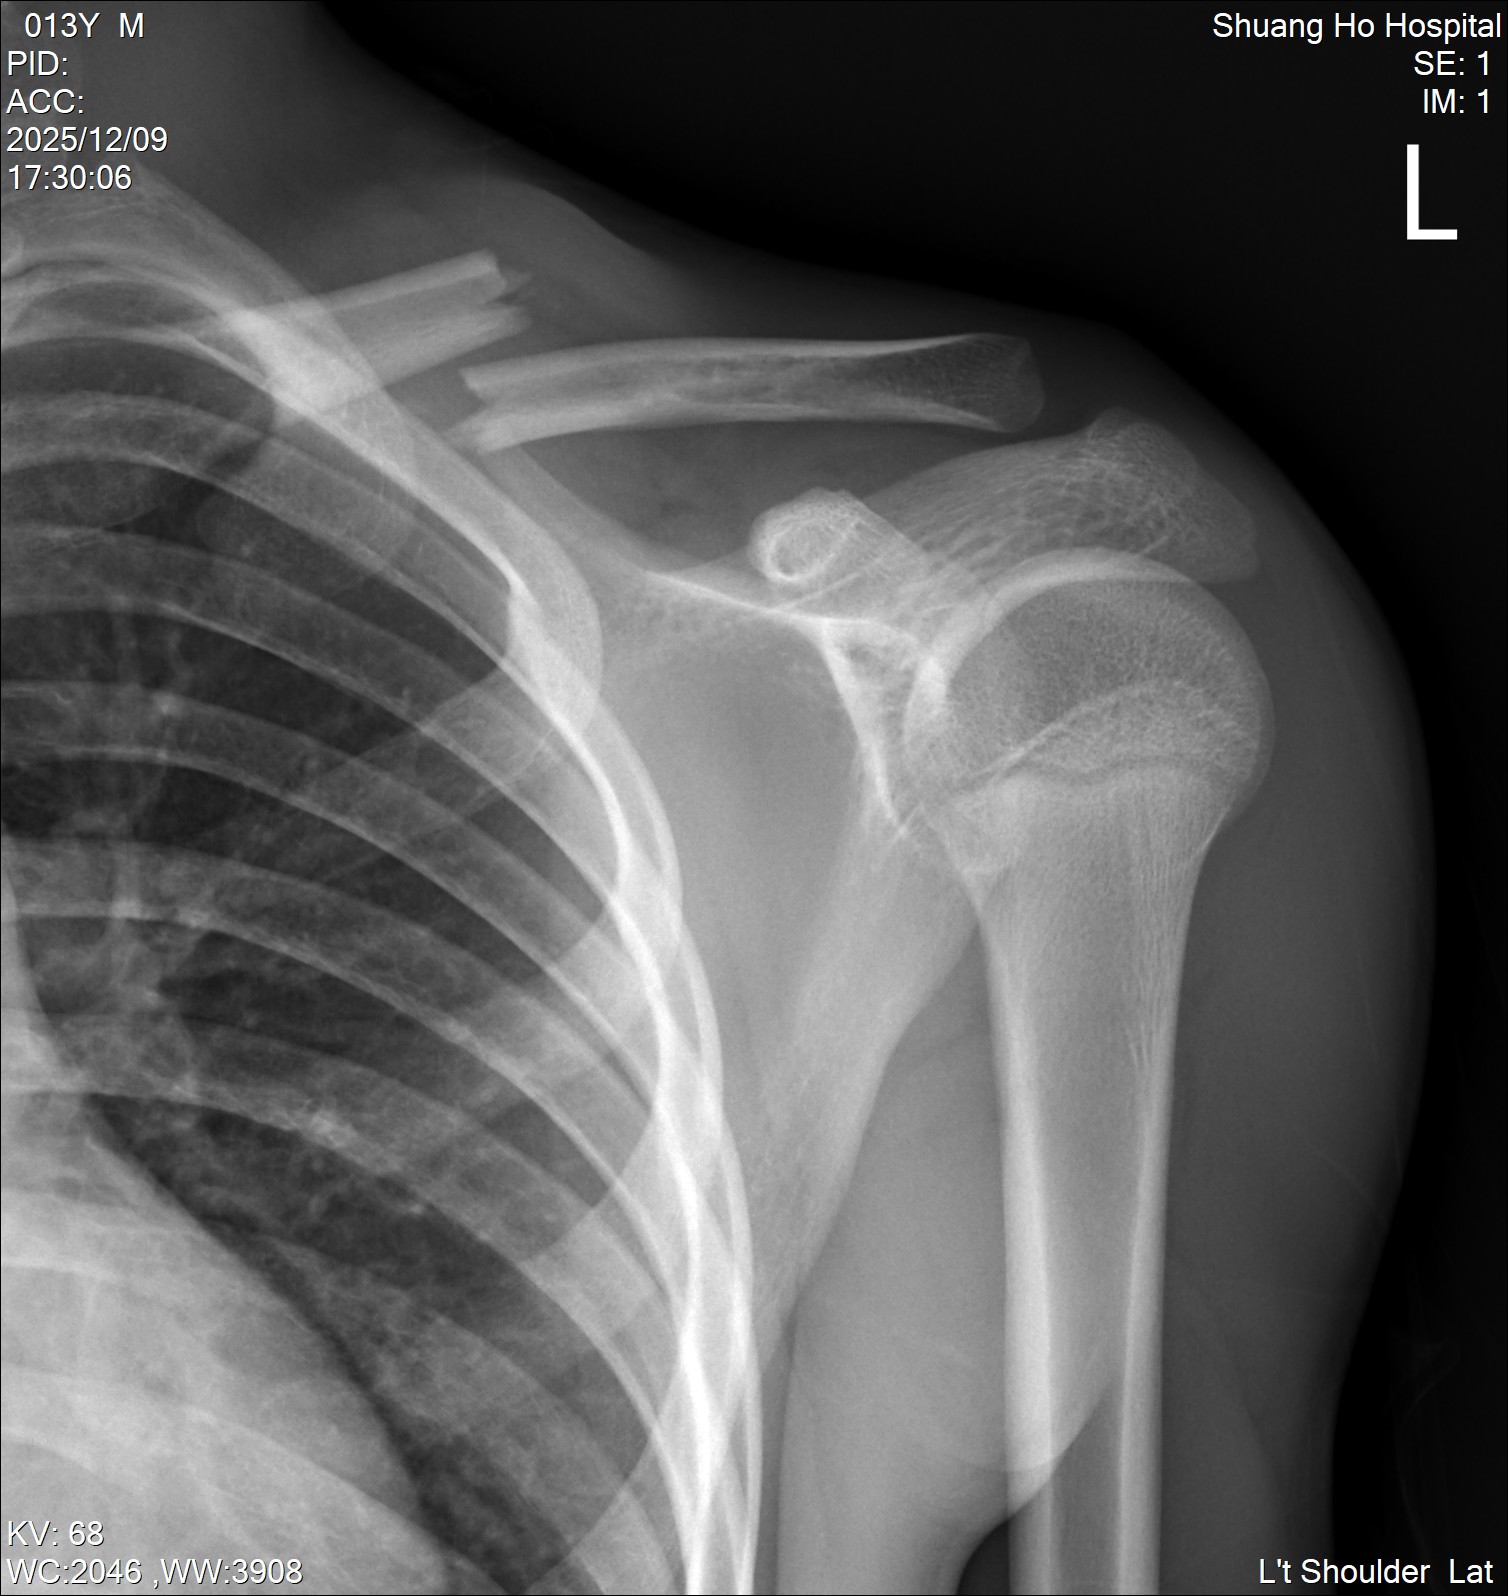

個案:13歲男孩,跆拳道練習時受傷,左側鎖骨骨折。經掃描確認鎖骨近遠端後,執行Clavipectoral fascial plane block,NRS 10 to 0。(圖片6、影片6)

圖片613歲男孩,跆拳道練習時受傷,左側鎖骨骨折

影片613歲男孩,跆拳道練習時受傷,左側鎖骨骨折。超音波掃描確認骨折近遠端後執行Clavipectoral fascial plane block